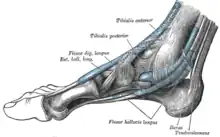

Les muscles extrinsèques du pied sont situés dans la jambe et seuls leurs tendons sont présents dans le pied. On distingue quatre groupes selon la position de ces tendons au passage de la cheville : postérieur, médial, antérieur et latéral.

Le groupe postérieur est constitué du tendon calcanéen issu du muscle triceps sural et permettant la flexion plantaire de la cheville ; il s'insère directement sur la partie postérieure du calcanéus. Le groupe médial passe en arrière de la malléole médiale et dans le rétinaculum des fléchisseurs, et se continue sur la face médiale et la plante du pied. Il comporte les tendons des muscles fléchisseur commun des orteils et long fléchisseur de l'hallux, qui permettent la flexion des orteils, et tibial postérieur, qui permet l'inversion du pied.

Le groupe latéral passe en arrière de la malléole latérale et dans le rétinaculum fibulaire, et se continue sur le bord latéral du pied. Il contient les tendons des muscles long fibulaire et court fibulaire, qui permettent l'éversion du pied.